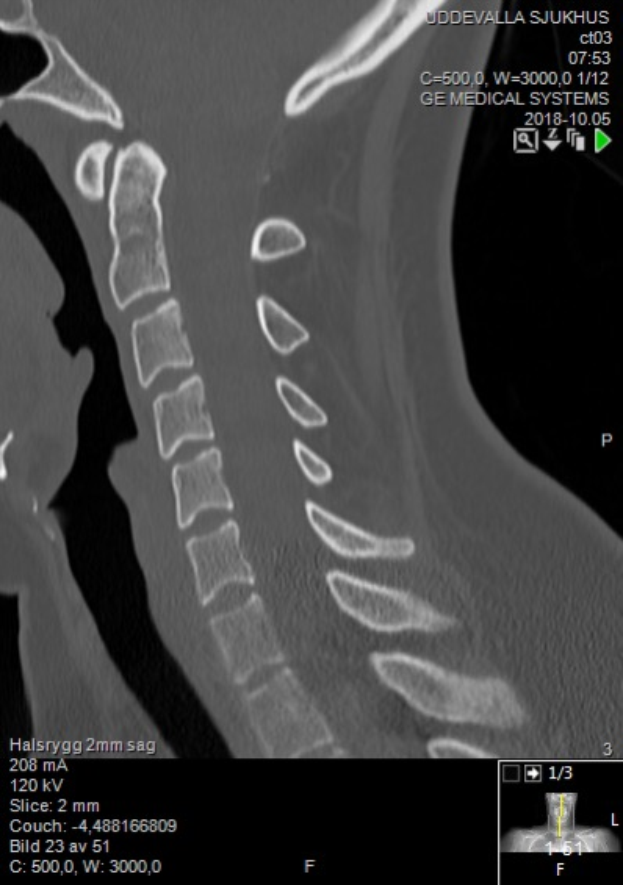

Ein Röntgenbild eines Mannes am Hals mit einem sichtbaren Bruch in der Mitte, das auf einem Computerbildschirm mit Text und Zahlen angezeigt wird.Gernot Gertz